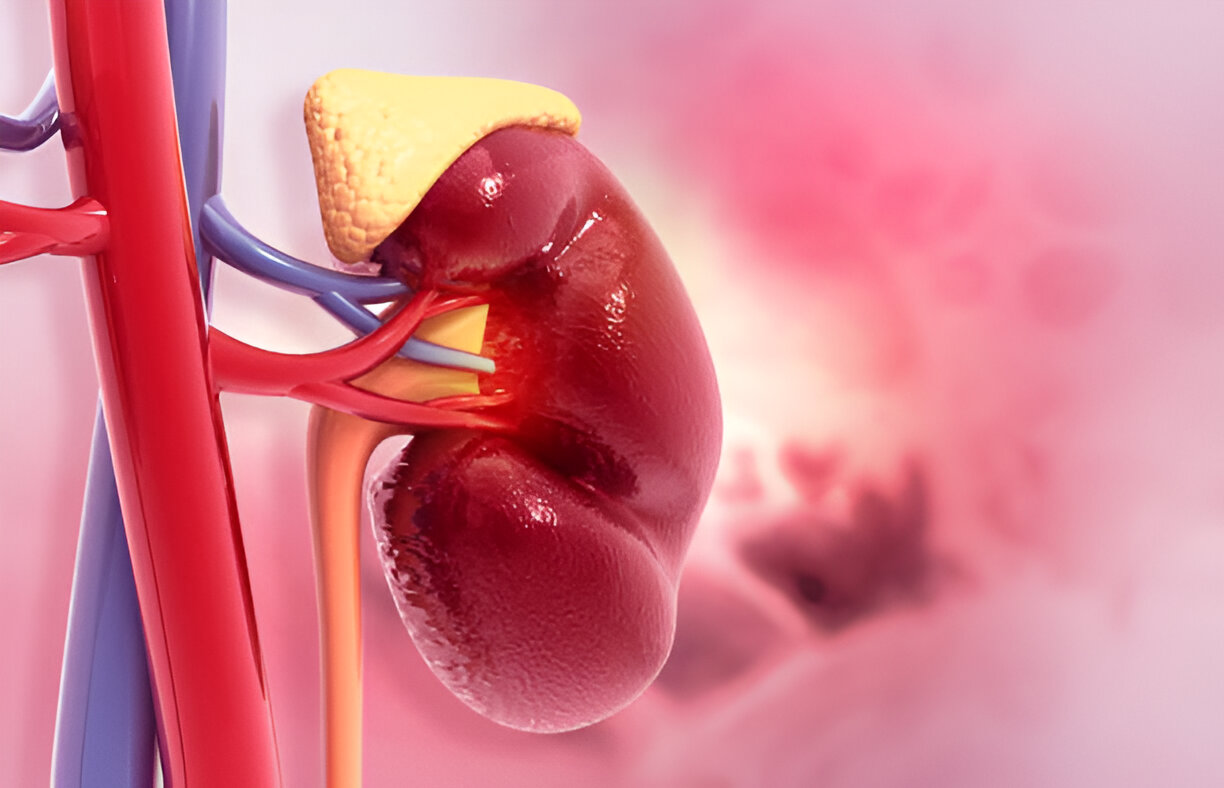

Adrenal glands ensure all hormones in your body are perfectly aligned. Adrenal glands are small, triangular shaped organs which are located above the kidneys and play a very crucial role in regulating the body’s stress response, blood pressure and metabolism.